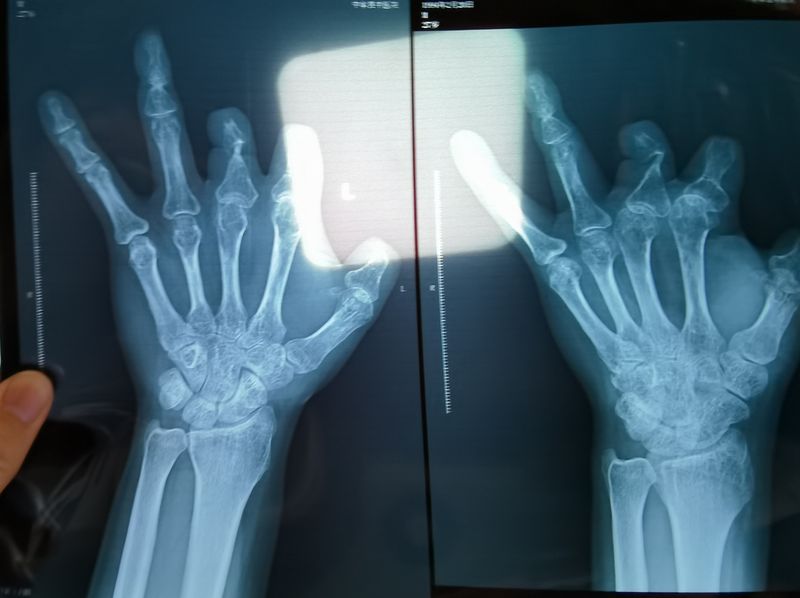

患者王海森左手拇指關(guān)節(jié)以上部位被電鋸切斷,收費單顯示術(shù)中使用了微血管吻合裝置,但X光片中未顯示該器械。新京報記者 程亞龍 攝

單價1.68萬元,聲稱在術(shù)中植入體內(nèi)、用于縫合血管的兩個環(huán)形吻合裝置,竟然在王海森的X光片上消失了。

裝置上帶有不銹鋼針,不可能被人體吸收,唯一的可能就是“手術(shù)時其實沒有使用”。盡管之前也有其他人向王海森透露過這一點,但直到看到片子前,他一直都不相信。

王海森稱,他出院約1年后,有人曾找到他說,這個價格昂貴的進(jìn)口器材,并沒有在手術(shù)中使用。當(dāng)時他沒有相信,直到2021年12月,經(jīng)人提醒,王海森在老家開封尉氏縣人民醫(yī)院拍攝了左手X光片,才確認(rèn)手術(shù)部位的確沒有微血管吻合裝置。2021年12月底,王海森向鄭州市公安局二七分局刑偵大隊報案。